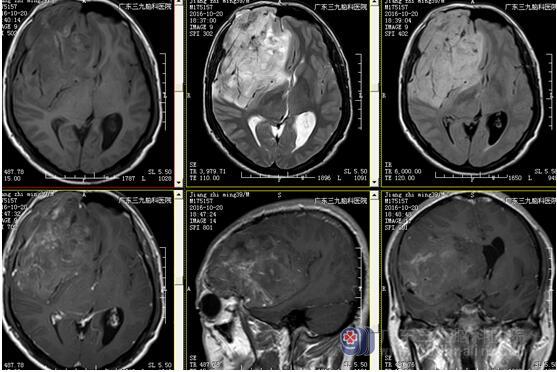

图3:术前磁共振显示肿瘤位置及大小约10.8×8.6×8.7cm

少突胶质细胞瘤无包膜,与周围脑组织界限清晰,50%-80%病例出现钙化,可散在或融合成较大的钙化小体,弯曲条带状钙化为其特征性表现,但广泛钙化罕见。本例肿瘤巨大(范围约为10.8×8.6×8.7cm),CT示斑片状低密度影及条带状典型高密度钙化影,病灶内及边缘示多发迂曲血管影沿钙化斑块走行,强化后呈轻度不均匀异常强化影,均符合少突胶质瘤典型影像学改变。